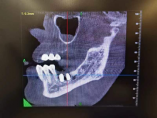

(锥形束CBCT为重建三围模型提供精准数据、计算机辅助设计软件辅助医生定制精准方案)

(李女士种牙经过)

数字化种植牙就是指利用数字化技术辅助医生进行种植修复。在种植牙诊断和设计阶段,通过CBCT和口内扫描获取患者的口腔软硬组织信息,利用计算机辅助设计技术进行颌骨模型的三维重建,并在重建的模型上进行种植手术方案的设计,确定最适合患者的种植手术方案。在种植体植入阶段,利用计算机辅助制造技术,设计制作出种植导板,精确控制种植体植入位置、角度及深度,使种植体的植入更加精确、微创、高效。在种植牙修复阶段,可以采用口腔扫描的方式进行印模制取,取代传统的咬牙印的方式,避免患者恶心,提高患者的舒适度。